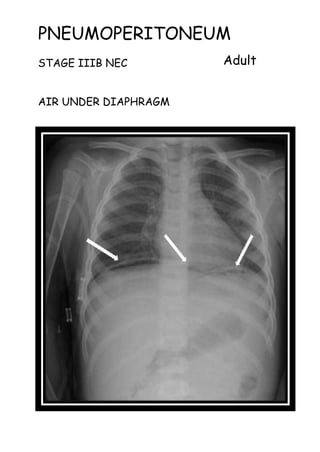

PNEUMOPERITONEUM

STAGE IIIB NEC

AIR UNDER DIAPHRAGM

Adult

The causes of neonatal

pneumoperitoneum are different from

adult pneumoperitoneum and include:

•perforated hollow viscus

• necrotising enterocolitis (NEC):

most common

• meconium ileus in cystic fibrosis

• Hirschsprung disease

• intestinal atresia or web

• peptic ulcer disease

•iatrogenic

• intubation/mechanical ventilation

• rectal thermometer

• enema

Radiographic features

Although these are essentially the

same as in adults, erect chest X-rays

are not obtained, and thus the

diagnosis should be made with supine

films. Additional horizontal cross

table shoot through films or left

decubitus shoot though films may be

performed.

Signs

•football sign

•Rigler's sign